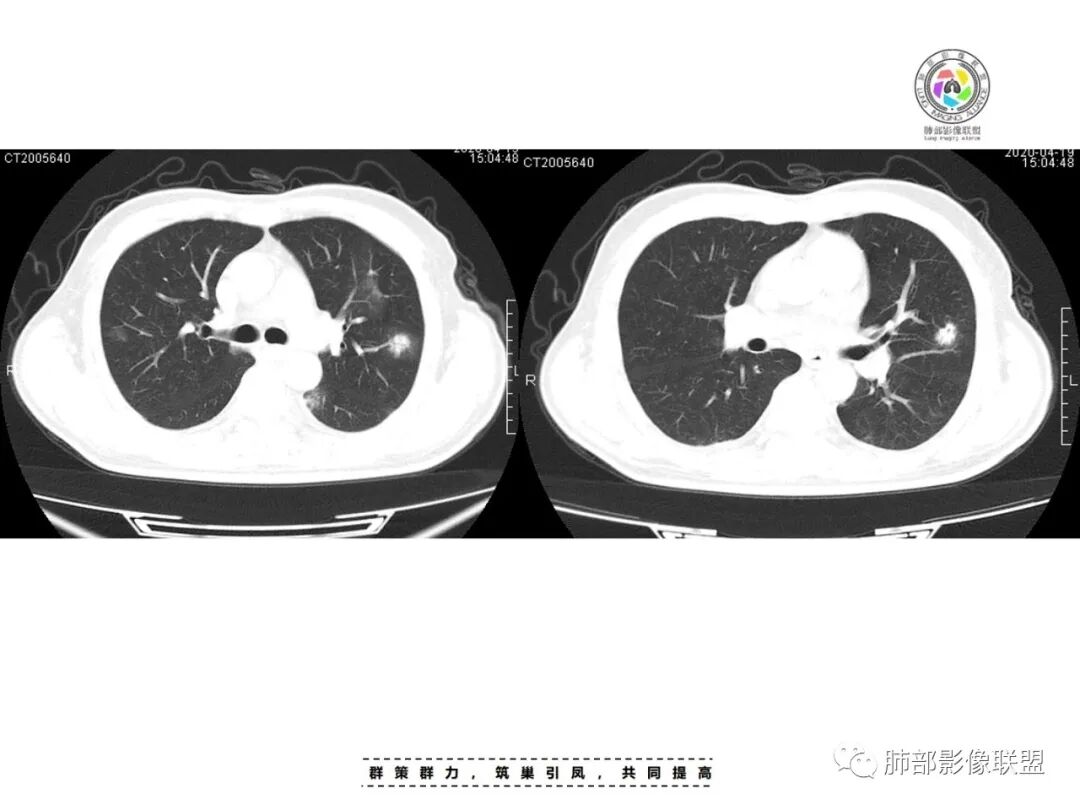

李:双肺多发结节,部分空洞,胸膜下为主,考虑血源性,治疗后好转,如果抗炎好转,考虑化脓菌栓,肺克或金葡,如激素治疗后考虑gpa亚东:双肺多发结节,部分见空洞,与血管关系紧密,考虑感染性病变,短期内变化快,糖尿病史,金葡,肺克?王秀仙:糖尿病基础上伴发的多发结节,部分空洞,四大金刚金毛结克,首选肺克琦遇:糖尿病四大金刚里按病史只有金葡和肺克符合,病灶特点,胸膜下为主,病灶偏少,有不干净空洞,肝功无异常,金葡可能性大!大雄:但是没有发热 小强:糖尿病史,胸膜下,6天空洞增大,金葡可能,肺克一般进展后有融合大片改变,这个没有,但是金葡临床症状更重,这个也看不出来崔少钢:中年男性,血糖控制不良,感染指标高。影像:双肺多发的结节、空洞,分布比较随机,考虑肺克。病变变化不够快,囊张力不够高,感觉不像金葡。大雄:血流感染的金葡 与肺克影像上有重叠,不一定好区分肺克炎性指标(PCT)可以高的更明显金葡血流感染一般有可追寻的来源,比如皮损,软组织脓肿,骨髓炎,心内膜炎等肺克一般是来源肠道,经门脉系统入肝,形成肉眼可见的肝脓肿或者不可见的隐匿性微脓肿,再经肝静脉回流→下腔静脉→右心→肺动脉→肺内播散张小兵:糖尿病基础,胸膜下多发结节伴空洞形成,这么大的空洞结节无播散,排除结核。肉芽肿性多血管炎,一般累及支气管,引起支气管狭窄,也可排除,倾向肺克,鉴别金葡。流心明智:男性,51岁,以咳嗽、咳痰、气喘3天。既往糖尿病10年。血常规wBC及中性比、CRP、PCT均升高。CT示:双肺多发结节、小斑片影,胸膜下多,大部分实性、部分伴空洞,大部分类圆形、部分呈楔形,部分病灶可见滋养血管征,治疗后逐渐吸收。考虑:感染性病变,SPE,金葡>肺克,鉴别隐球、TB等。

一、双肺多发结节或小片影,随机分布,而未见支气管壁增厚及支气管远端如树芽征等改变,提示病灶来源于血道;且肺内结节边缘模糊,常可排除转移(一般转移瘤边缘多较光整,患者常有恶性肿瘤病史,且呼吸道症状不明显或出现较迟);

首先看金葡菌,金葡菌多数要有皮肤受累感染才能入血,而该例没有相应病史,只是受凉。况且金葡感染患者易出现高热、病情进展更迅速,而该患者体温36.5摄氏度,不符合;影像上金葡更易短期内出现张力较高的薄壁气囊及脓胸等;所以金葡可能性较小。

影像表现:双侧结节,常伴空洞形成,最多见于肺外周和肺下野,结节的边界清晰或模糊;可伴有斑片状实变区;多表现为基底贴近胸膜的楔形实变影,其内密度均匀或不均匀,可形成空洞。